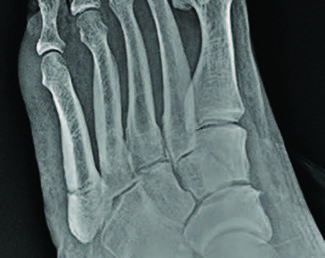

William D. Fishco, DPM, MS, FACFAS; Mahsa Agha Jafari, DPM, AACFAS

Fifth metatarsal fractures are relatively common injuries, but athletes in particular require a unique approach. Here the authors share their experience and evidence from the literature, including classification, examination, imaging and...